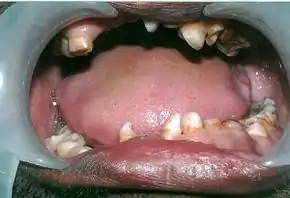

- The permanent teeth include supernumerary teeth. Unless these supernumeraries are removed they will crowd the adult teeth in what already may be an underdeveloped jaw. If so, the supernumeraries will probably need to be removed to make space for the adult teeth. Up to 13 supernumerary teeth have been observed. Teeth may also be displaced. Cementum formation may be deficient.[13]

- Failure of eruption of permanent teeth.

Panoramic view of the jaws showing multiple unerupted supernumerary teeth mimicking premolar, missing gonial angles and underdeveloped maxillary sinuses in cleidocranial dysplasia.